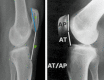

Today, total knee arthroplasty (TKA) is one the most commonly performed surgeries worldwide. The purpose of this article is to review the appearance of normal post-TKA roentgenographs and describe the correct sequence for their interpretation. It is unwise to depend solely on patients' symptoms when diagnosing TKA complications because serial radiographs can foresee failures well before they manifest clinically. Ideal post-TKA radiographs comprise whole lower extremity anteroposterior and lateral views taken under weight bearing conditions along with a skyline view of the patellofemoral joint. Among other things, weight bearing exposes the true alignment, ligamentous laxity and polyethylene wear. On the basis of follow-up of our TKA cases, we have drawn up a protocol for assessing postoperative X-ray films after TKAs. Following the proposed sequence, surgeon can easily decide how to proceed with follow-up and foresee complications. Careful interpretation of postoperative radiographs after TKA is essential to careful monitoring of patients and implant survival.